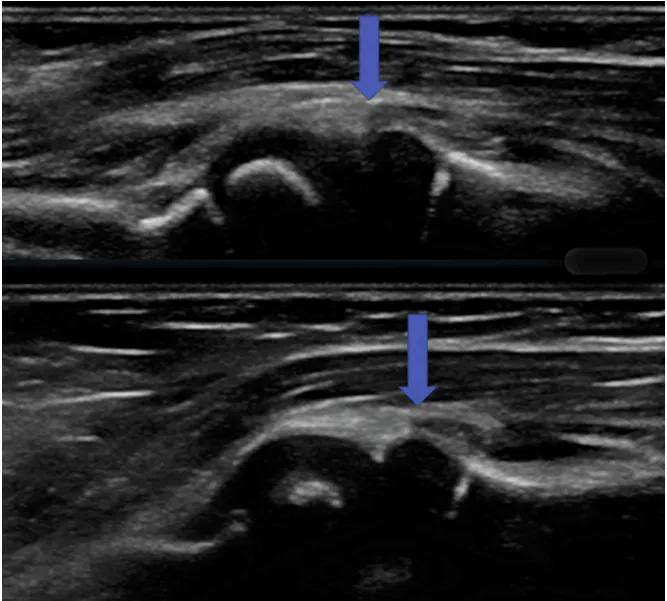

B2. 초음파 진단. Antecubitum 부분을 US 로 관찰한다

(1) Pulled elbow 시 US 소견

화면의 왼쪽 편에 상완골의 말단과 Capitellum 이 보이며,

화면의 오른 편에 Radial Head 가 관찰됨.

위 그림 : radiocapitellar joint로 끌려 들어간 Supinator muscle (supinator가 radial head를 넘어감)

아래그림 : 정복술 후. Supinator 가 radial head를 넘어가지 않는다.